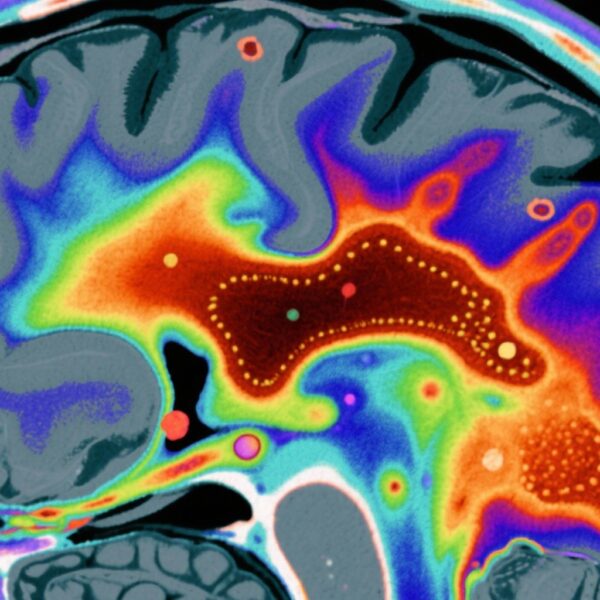

This investigation utilized data from the Mental and Substance Use Disorders Prevalence Study, a nationally representative household sample of nonelderly US adults (N=4,764). Participants underwent clinician-administered Structured Clinical Interview for DSM-5 (SCID-5) assessments to determine past-year and lifetime prevalence of SSDs, including schizophrenia, schizoaffective disorder, and schizophreniform disorder, as well as to identify positive psychotic symptoms.